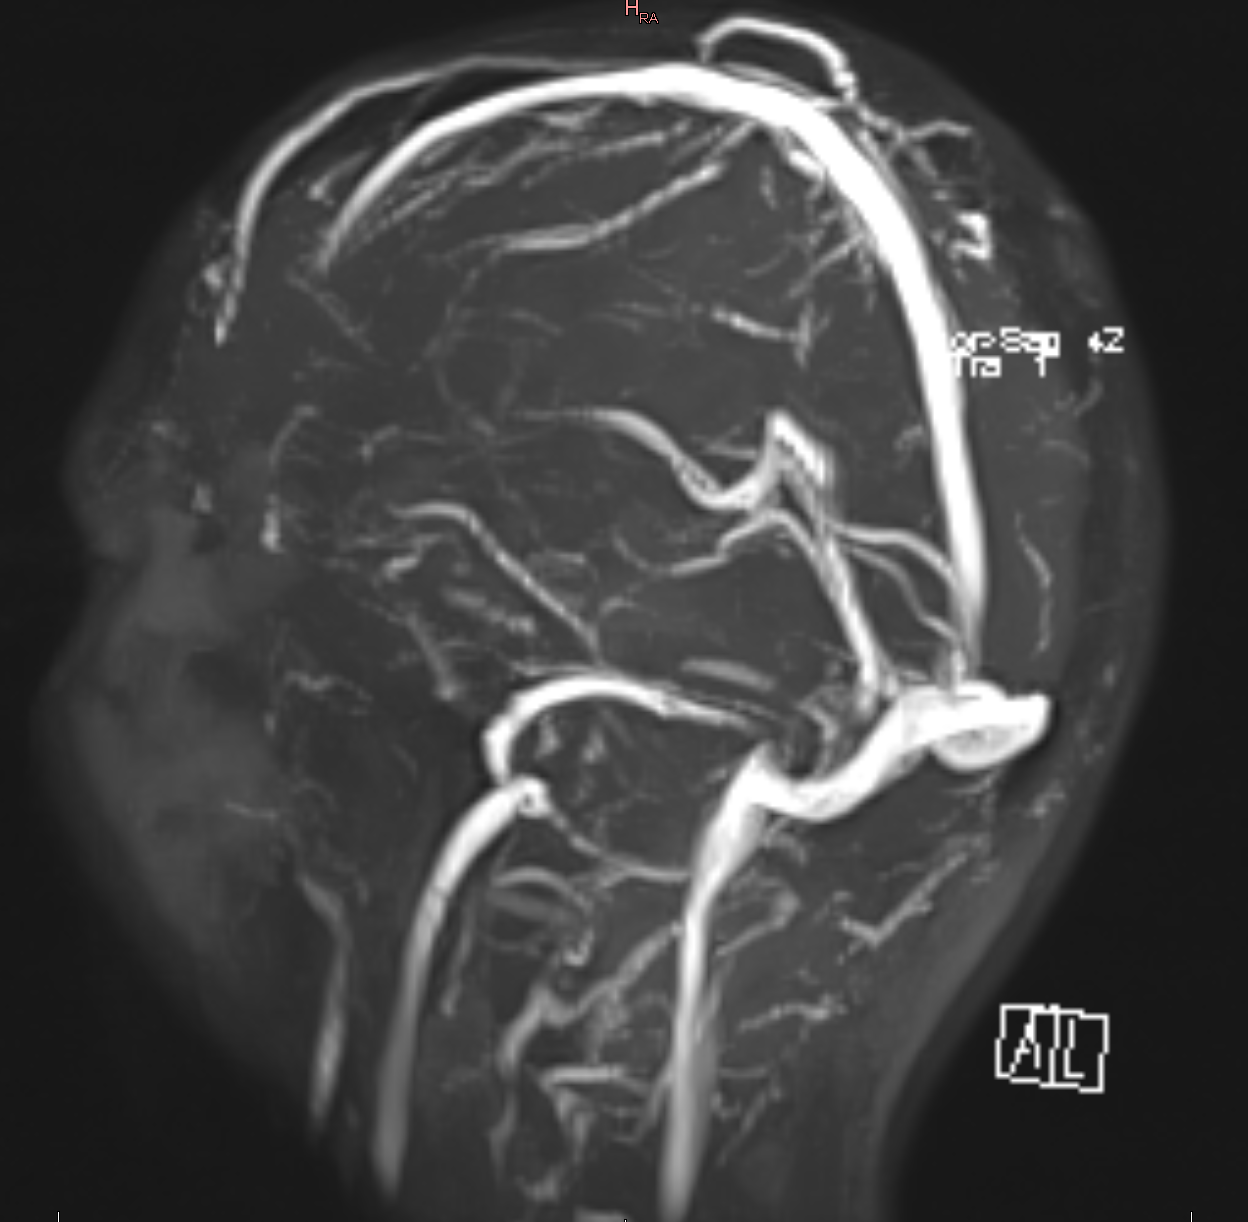

1744085122193.jpg 845Кб, 3418x1039

3418x1039

1744085122219.jpg 1178Кб, 3780x1562

3780x1562

Аноны, умоляю, успокойте меня. Где-то пол месяца чувство распирания в висках и между бровями выше ко лбу, иногда головокружения, особенно когда долго сижу. Ещё состояние такое, будто в полусне нахожусь. На пиках ЭЭГ и РЭГ, сегодня сделал. Ещё делал рентген, ничего не показал. Имею остеохондроз шеи первой степени и гипертонию первой степени, курю, довольно много хожу пешком. Моторика не нарушена, перепадов настроения нет, речь не нарушена, память не нарушена. Анализы крови и мочи нормальные.

Умру завтра или ещё поживу?

>>1614056

Я ставлю на слабое кровоснабжение ГМ по причине остеопроблем шеи, с ущемление корешков и отсюда ангиопроблемы.

Либо следствие препаратов для снижения АГ.

Но так как ты балаболка, и р-снимков не показываешь, а верить дебилам на слово нельзя, то советую взять все снимки и анализы и идти к специалисту на прием.

Поживешь, и довольно долго, пока не поймаешь ГТ криз.

Тут еще в теме есть обиженные, спроси их, только вежливей с ними будь, они догматики.

1744096603483.jpg 938Кб, 4294x959

4294x959

>>1614067

Спасибо за ответ. Самих рентген-снимков у меня нет на руках, есть только пикрил заключение. Пойду завтра к неврологу тогда

Аноним 08/04/25 Втр 10:26:59 1614072 207

> попросили пруфы в споре

> ряя обиженные пок пок догматики

Аноним 08/04/25 Втр 10:28:17 1614073 208

Нет серьезно посоны, этот невролог ведь вас и к мануальному отправит, и к ведунье в деревню, опасный человек

Аноним 08/04/25 Втр 10:55:10 1614077 209

>>1614073

Но я же отправил его к специалисту, то есть, к тебе. Хотя, такой как ты опять включит обиженного бюрократа, и выпишет ему шрот подорожника и афобазол. И сравнение себя с аферистами - забавно. Прямо в точку. Когда придет, еще и промиков ему дай в онлайн-аптеку. Не забывай про план продаж мерча.

Аноним 08/04/25 Втр 10:59:08 1614079 210

>>1614071

Значит, ущемление отбрасываем. Зато можно отправить к сосудистым, проверять просвет артерий и вен шеи и основания черепа.

Но так как с дебила надо тянуть еще и список препаратов, продолжаем санта-барбару с опросом или допросом. Что принимаешь? Помимо сигарет.

Аноним 08/04/25 Втр 11:04:10 1614081 211

>>1614079

>Зато можно отправить к сосудистым, проверять просвет артерий и вен шеи и основания черепа

Ой, пропустил. После ЛФК.

>вас и к мануальному отправит

Советую мануального, по совету этого господина врача.

Аноним 08/04/25 Втр 13:18:32 1614099 212

1744107457730.jpg 1779Кб, 3086x2632

3086x2632

Сканирование вен шеи делал, пикрил результаты. От гипертонии ничего курсового сейчас не пью. Раз в несколько месяцев, когда подскакивает давление, принимаю одну таблетку моксонитекса. До результатов ЭЭГ и РЭГ невролог прописал Мидокалм 450 мг в сутки (не помог) и Фенотропил по одной таблетке в день (эффекта не заметил, но до сих пор принимаю).

Ещё имею полиостеоартроз лучезапястного и пястно-фаланговых суставов правой кисти гитарист со стажем, примерно месяц принимаю Диацереин 50 мг в сутки, Артра МСМ две таблетки в сутки, ну и витамин D. Но в побочках этих препаратов ничего похожего на моё текущее состояние нет.

Аноним 08/04/25 Втр 14:00:27 1614108 213

>>1614099

Я же пишу - Санта-Барбара, серия 3, скоро появится КТ\МРТ.

Спроси местных специалистов, как бы они стали лечить синдром ПА, вызванный лордозом, на фоне легкой гипоплазии ПА, с динамической коморбидной ишемией мозга из-за сужения и курения, с развитием артериальной гипертензии. Бери все документы и иди к настоящему невропатологу и вертебрологу. Тут врачей нет.